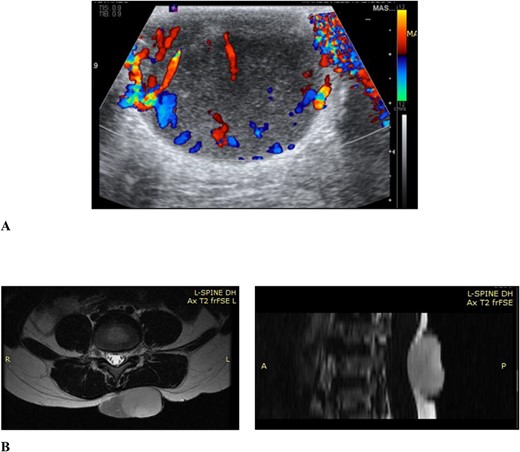

Ultrasound examination revealed a well-circumscribed heterogenous lesion measuring 4.8 × 4.0 × 2.9 cm, with areas of increased flow on doppler imaging but no vascular pedicle, phleboliths nor calcifications (Fig. 2). Magnetic resonance imaging (MRI) examination showed a well-defined 5.4 × 4.6 × 2.7-cm lesion, centred in the subcutaneous tissues of the back, extending to the erector spinae fascia but not crossing it and no tract to the spinal canal (Fig. 2).

(A) Ultrasound scan of the lesion to the lower back with doppler showing vascular flow; (B) MRI scan of the lesion to the back showing it extending to the level of the erector spinae fascia but not crossing it and no tract to the spinal canal, in the axial and sagittal planes, respectively.